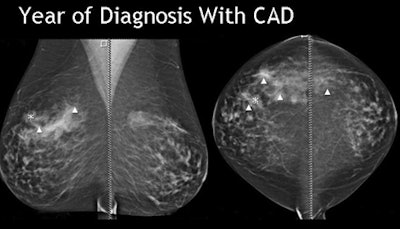

The study evaluated the effectiveness of digital mammography CAD in marking breast cancers both at diagnosis and in prior years' scans. The retrospective review examined all interval missed cancers from 2004-2008, Destounis said.

At diagnosis CAD marked 78% (47) of the cancers, Destounis said. CAD marked 70% of the masses, 80% of masses with calcium, and missed the case of architectural distortion.

Thirteen of the 60 cancers were not detected by CAD in any view, including 11 masses, one mass with calcium, and one case of calcium with architectural distortion. There were 11 biopsy-proven invasive ductal carcinomas, one biopsy-proven atypically papillary neoplasm or DCIS, and one biopsy-proven metastatic malignant melanoma.

"CAD marked the area of cancer 47% of time (n = 24) on the prior most recent mammo, and in fact there was one case where the cancer was marked on two prior years," Destounis said. But in all cases of prior findings, either "we didn't pick it up or we didn't mark it," she said.

Overall, CAD marked the cancer 78% of the time, and cancer in prior year(s) 40% of the time, she said. So the study showed that even when CAD marked the lesion of interest, radiologists continue to disregard the CAD marks frequently, she said. Why is this happening?

"The area may be a lower threshold of concern for the radiologist reading or for both of us reading at the same time," Destounis said. "Or we're distracted by something else. Frequently I'm working up the cyst on the other side, or the calcium that turns out to be benign, or a core biopsy. So I guess satisfaction of search is a factor," she said.